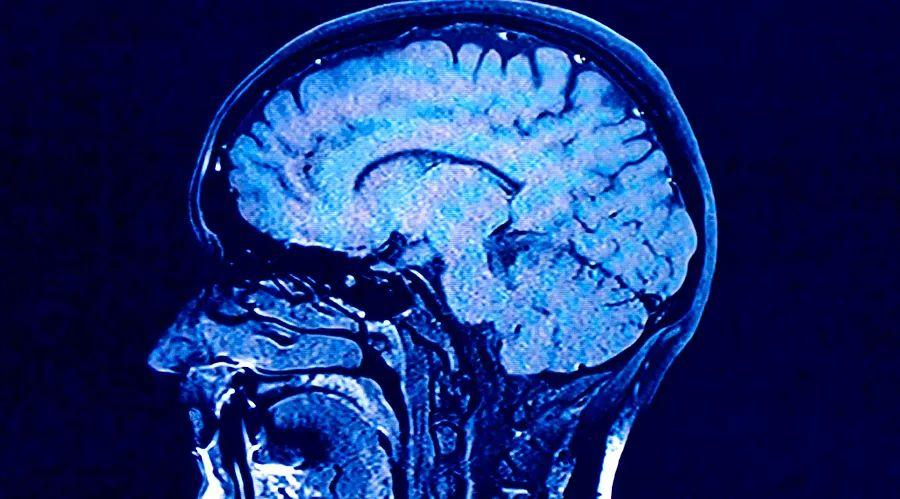

"We first conducted MRI scans of participants when they were 73 years old. What struck me most about the study was the vast differences between their scans," Cox wrote.

"Even though they were all the same age, some brains appeared perfectly healthy—similar to those of individuals in their 30s or 40s—while others displayed significant shrinkage and damage to the white matter, along with other signs linked to cognitive aging and dementia," he said.

White matter forms the connections between brain cells and the nervous system, enabling communication through nerve signals. Loss or damage to this tissue can impair the brain's ability to process information.